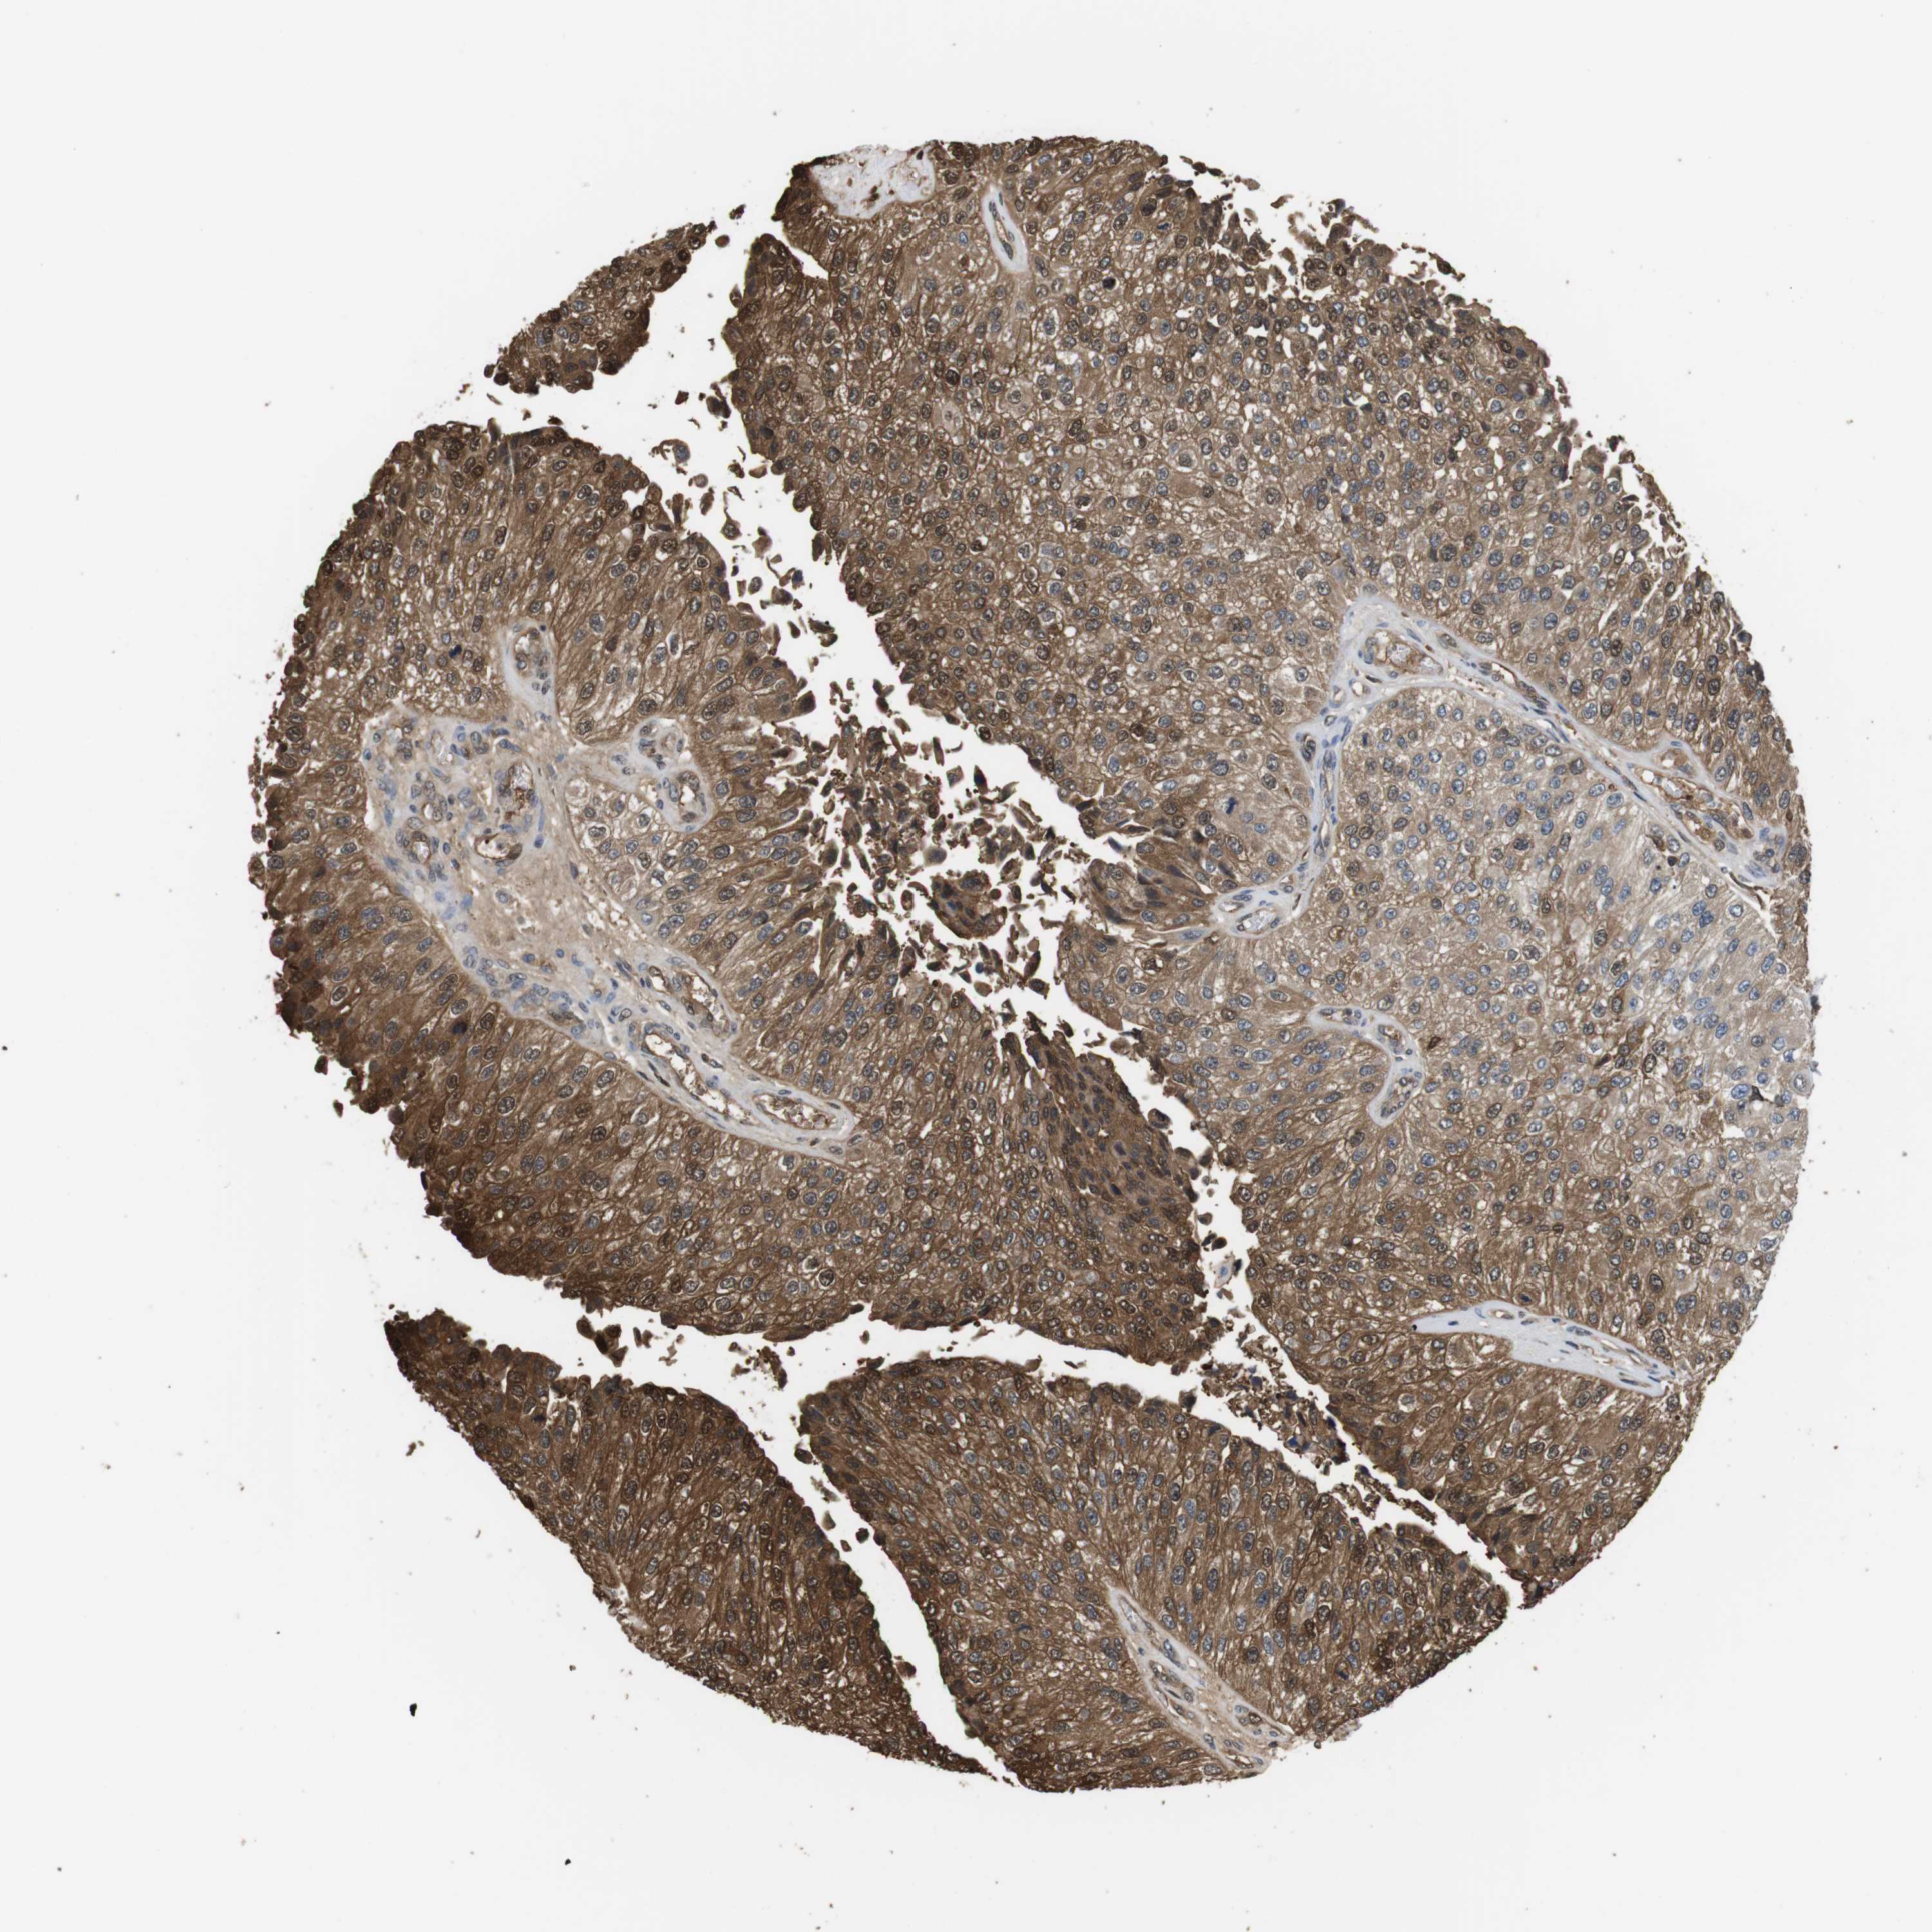

UROTHELIAL CANCER - Protein expressioni

A mouse-over function shows sample information and annotation data. Click on an image to view it in a full screen mode. Samples can be filtered based on level of antibody staining by selecting one or several of the following categories: high, medium, low and not detected. The assay and annotation is described here.

Note that samples used for immunohistochemistry by the Human Protein Atlas do not correspond to samples in the TCGA dataset.

Antibody stainingi

Antibody staining in the annotated cell types in the current human tissue is reported as not detected, low, medium, or high, based on conventional immunohistochemistry profiling in selected tissues. This score is based on the combination of the staining intensity and fraction of stained cells.

Each image is clickable and will lead to virtual microscopy that enables deeper exploration of all samples and also displays staining intensity scores, fraction scores and subcellular localization as well as patient and tissue information for each sample.

Antibody CAB015336

Antibody CAB069404

Staining

High

Medium

Low

Not detected

Intensity

Strong

Moderate

Weak

Negative

Quantity

>75%

75%-25%

<25%

None

Location

Nuclear

Cytoplasmic/membranous

Cytoplasmic/membranous,nuclear

Urothelial carcinoma, High grade